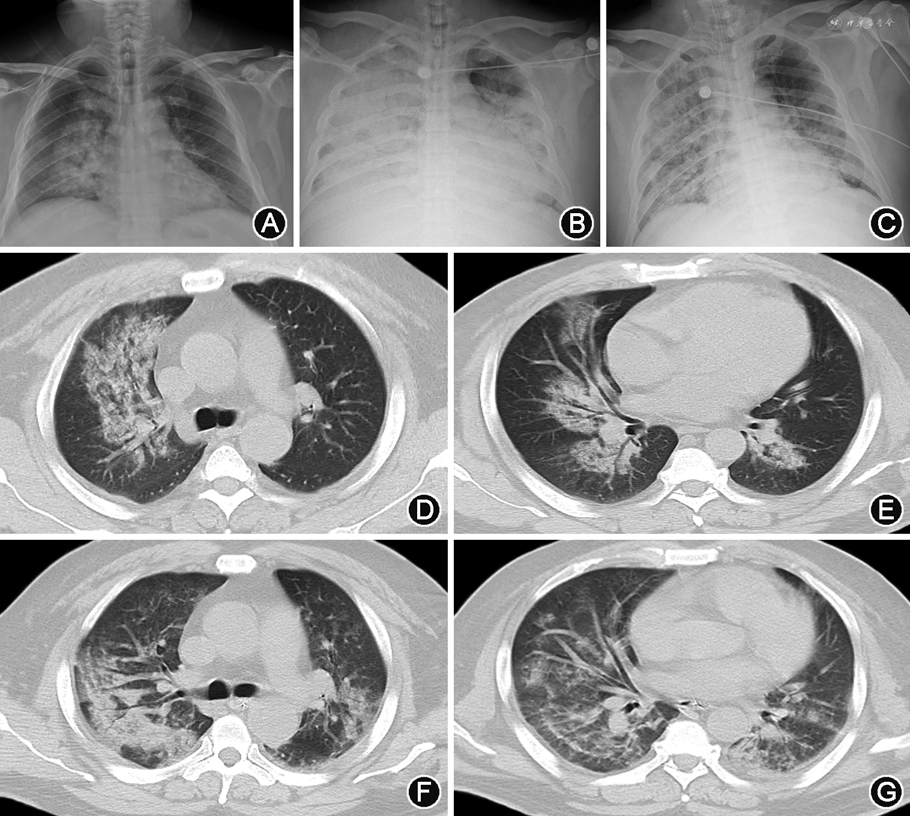

1. 重症病例:(1)X线:双肺受累多见,多发生在下肺[11, 12]。双肺纹理模糊,局限性或弥漫性分布的磨玻璃样改变及实变,部分可见弥漫性网状或结节状阴影。病程进展,病灶范围扩大,单侧病变可进展为双侧病变,单灶或多灶病变可进展为弥漫性病变,磨玻璃改变可融合为大片状实变[13]。可伴有胸腔积液[13]。合并肺气肿时,在病毒性肺炎基础上可见肺野透光度增强;合并细菌性肺炎时,表现为局灶性片状高密度影(图1)。(2)CT:单纯甲型H1N1流感重症肺炎病变常累及多个肺段及肺叶,病变可随机分布,但以双肺中下部周边为主[14, 15, 16, 17]。病变多表现为GGO和实变,或二者混合存在。磨玻璃阴影多位于周边,实变多靠近肺门,其内可见空气支气管征[18, 19, 20, 21](图1、2)。随病情进展,GGO会转化为实变,实变吸收也会转变成GGO。此外,还可见支气管血管束增粗、牵拉性支气管扩张等表现[16,22, 23](图3)。小叶间隔增厚、小叶中心结节等表现由于病情进展常常被掩盖,恢复期可见[24]。肺门及纵隔淋巴结肿大、胸腔积液和胸膜增厚等表现相对少见[25, 26]。肺栓塞亦可见,且发生风险较高[11,27]。可合并其他细菌性肺炎,进而形成合并性影像表现[12, 13,17]。治疗后恢复吸收阶段,病灶大多数可吸收,呈肺内广泛条索状、斑片状改变,甚至消失,部分病灶残留纤维瘢痕[22, 23]。

2. 危重病例:多表现为大片状或弥漫性病灶,在重症病例影像表现基础上,以实变为主,也可以合并肺不张和“白肺”改变[13,15, 16, 17,23,28, 29],少数病例可见胸腔积液[25, 26]。病程多进展较快,需要机械通气,继发纵隔气肿、皮下气肿及气胸[11,23,30](图4、5)。同时也常常合并其他感染及并发症,如肺栓塞等[11,30]。